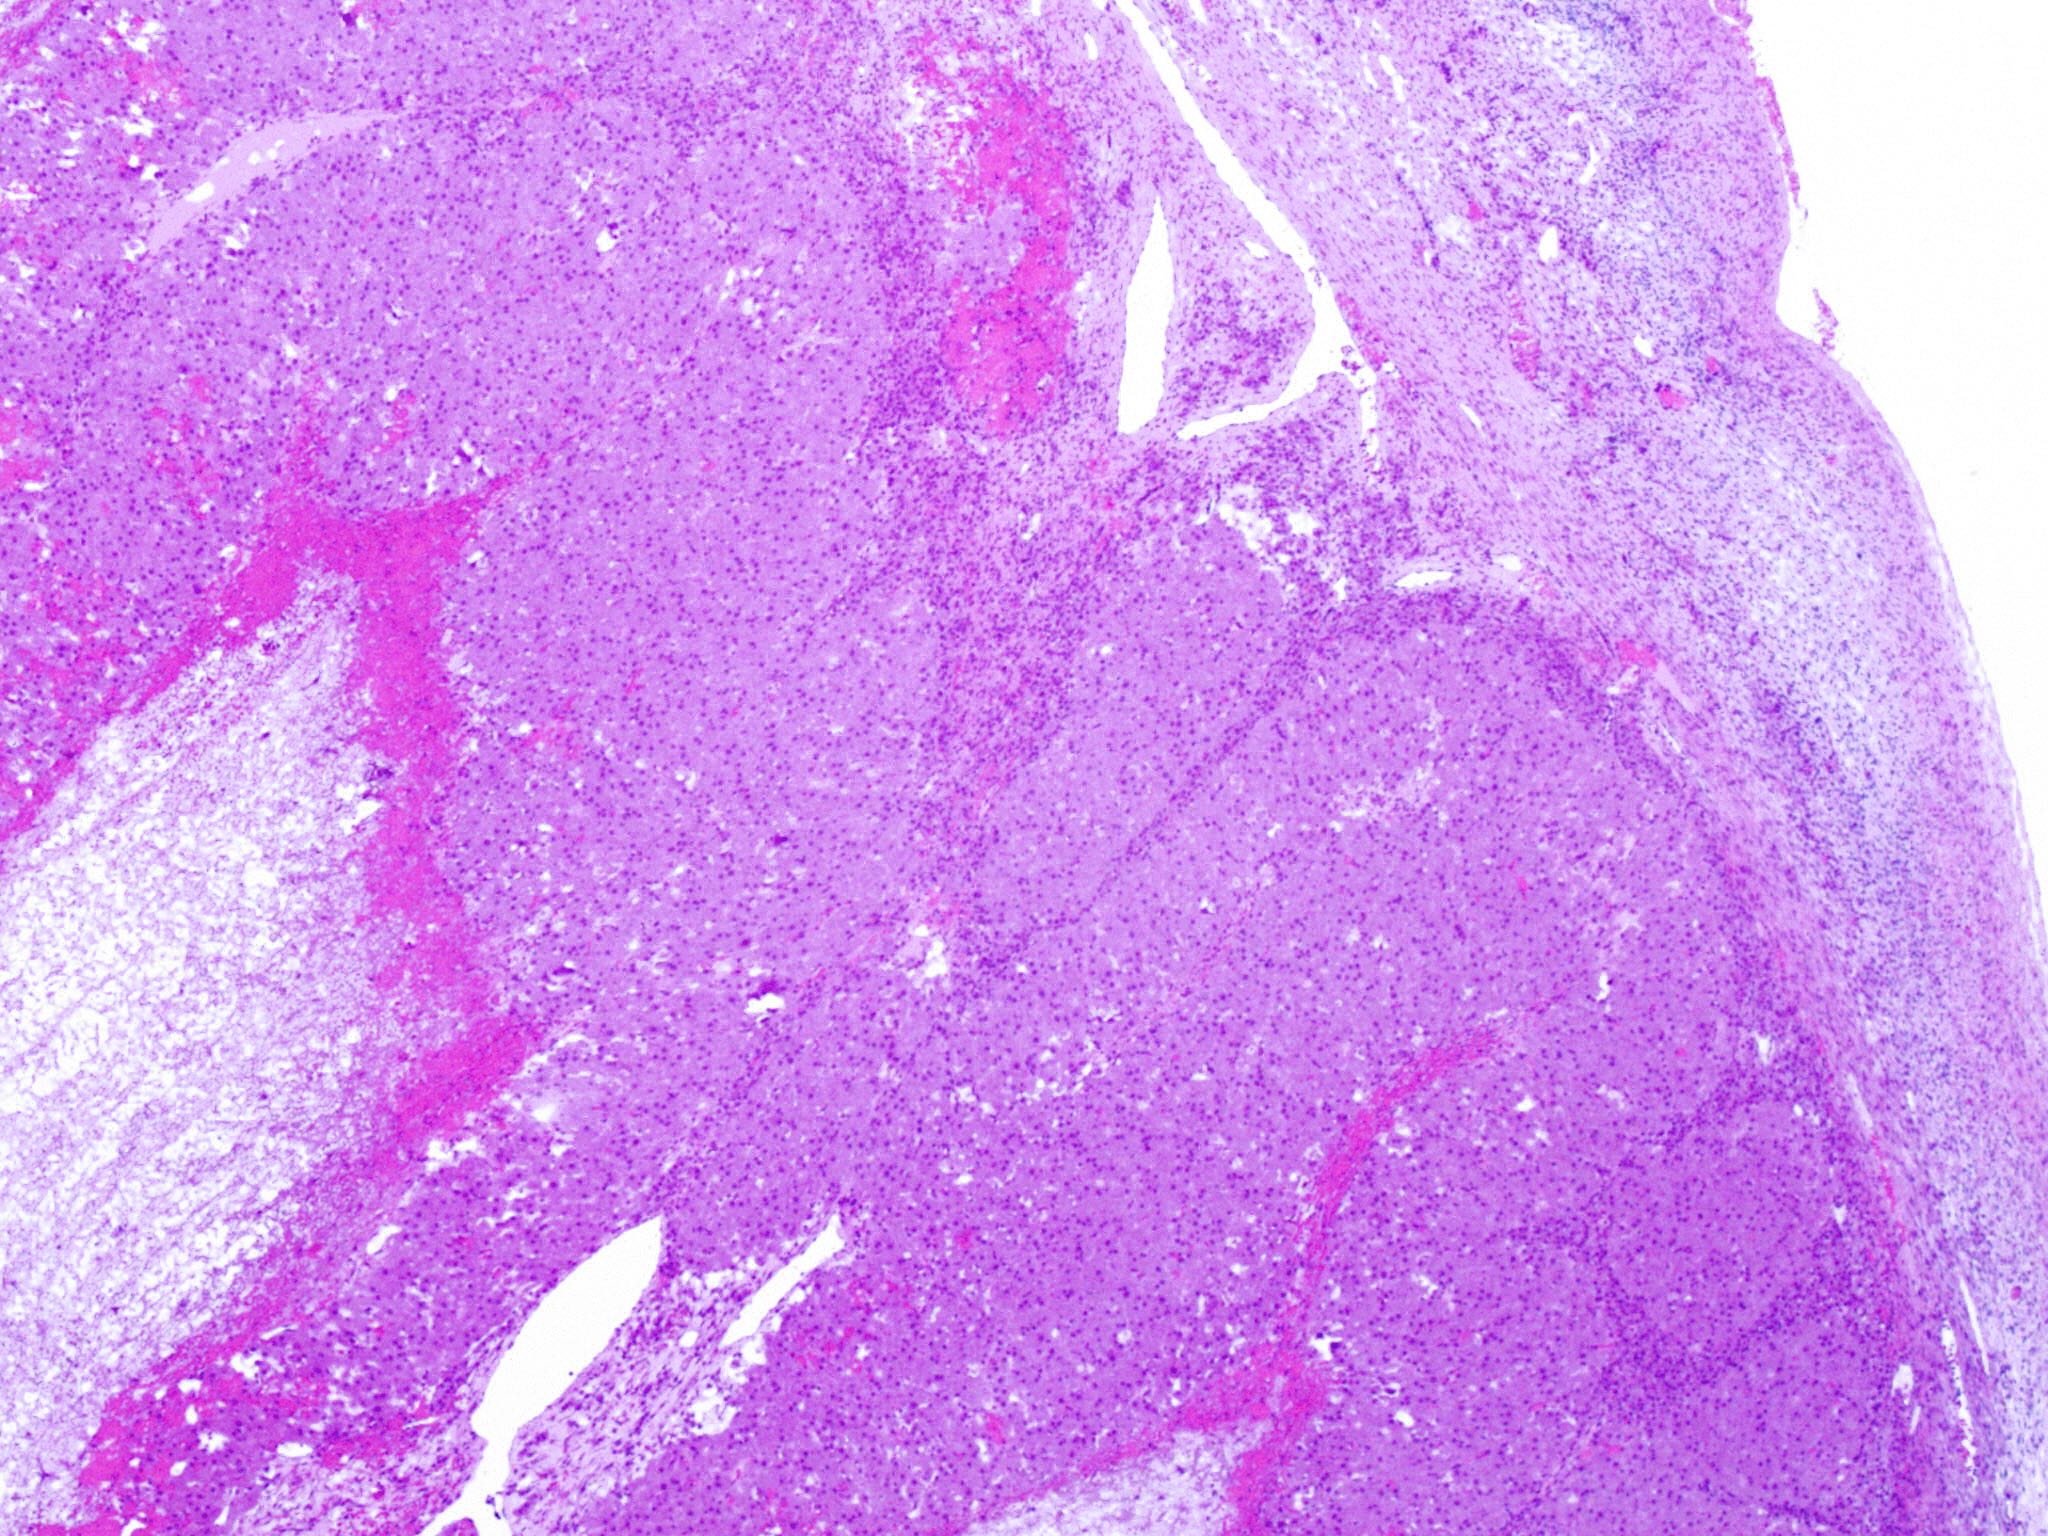

Microscopic (histologic) description

- Cyst lining is convoluted, composed of an inner layer of luteinized granulosa cells and outer layer of theca cells

- Granulosa cells are polygonal in shape, with abundant eosinophilic cytoplasm and central round nuclei

- Mitotic figures may be seen in the granulosa cells

- Outer theca cells are smaller in size

- Prominent inner layer of fibrous tissue

- Reference: Kurman: Blaustein's Pathology of the Female Genital Tract, 7th Edition, 2019

Microscopic (histologic) images